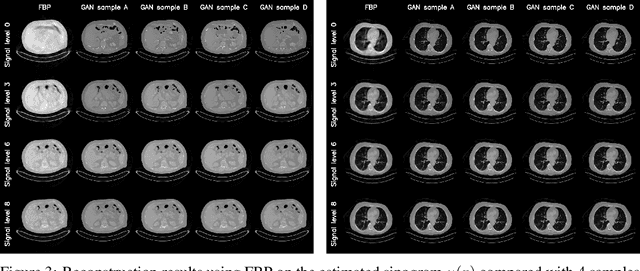

Abstract:We propose an end-to-end differentiable architecture for tomography reconstruction that directly maps a noisy sinogram into a denoised reconstruction. Compared to existing approaches our end-to-end architecture produces more accurate reconstructions while using less parameters and time. We also propose a generative model that, given a noisy sinogram, can sample realistic reconstructions. This generative model can be used as prior inside an iterative process that, by taking into consideration the physical model, can reduce artifacts and errors in the reconstructions.